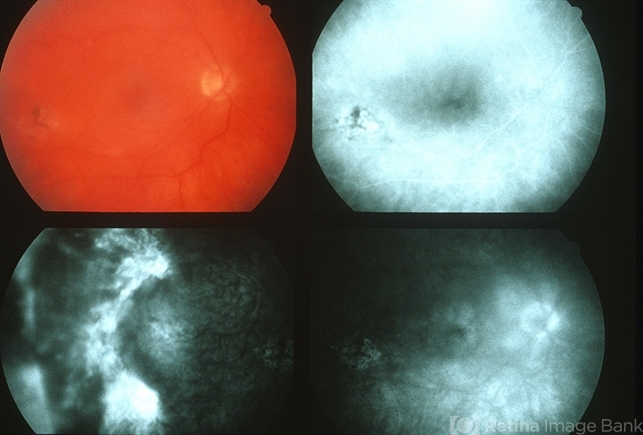

- acute retinal necrosis

- III ARN (RX'd); right eye: 20/80; left eye: 20/25.